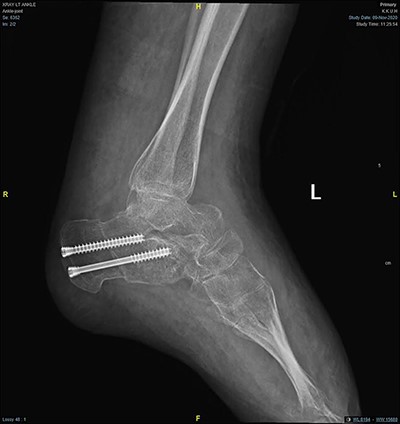

Magnetic resonance imaging (MRI) brain and whole spine were ordered for her due to the neurological pattern of the disease. The MRI showed T4–T5 posterior fusion, there were no other neurological lesions. For evaluation of the varicose veins, vascular consultation was obtained, and Doppler ultrasound was ordered, which showed absent popliteal deep veins. Radiography of the left foot revealed marked cavus as well as hindfoot and forefoot varus. Also, it showed soft tissue swelling, reduction in bone density, and no evidence of fracture or dislocation or tarsal coalition (Fig. 2). The right foot radiograph was unremarkable apart from mild hallux valgus deformity (Fig. 3).

Lateral weight bearing radiograph showing severe pes cavus with osteopenia and soft tissue swelling.